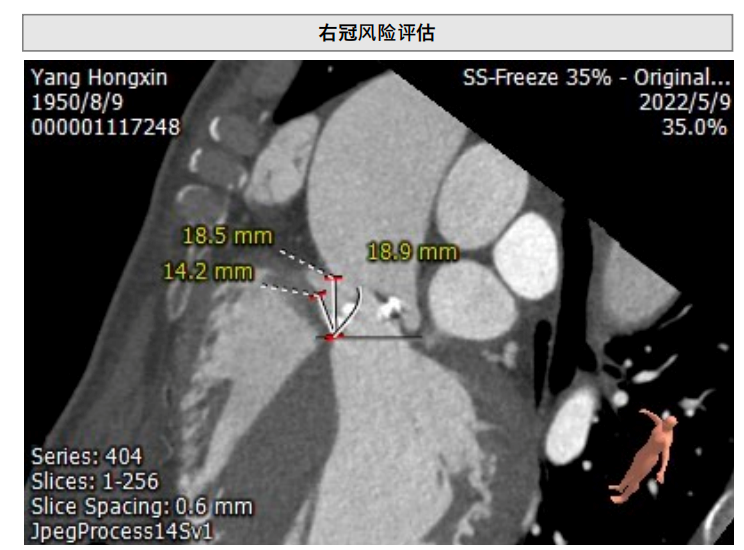

CT评估

主动脉根部CT测量

左冠高度:11.7mm

右冠高度:14.2mm

图片